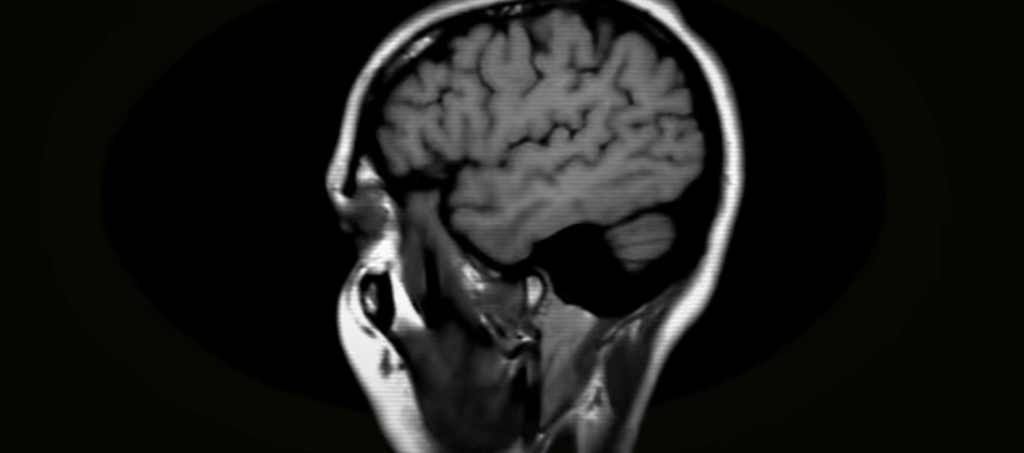

The traditional theory, according to which the brain retains information like a filing cabinet, has subtly collapsed. It is being replaced by something much more responsive, organic, and remarkably human. Scientists are learning that our brains shape information through failure, agency, and flexibility rather than just repetition thanks to behavioral study and fine-grained brain imaging.

We’re also learning that memory and emotion are closely related. Neuroscientists now know that the hippocampus, the memory center of our brain, enhances retention when motivation and engagement are high. On the other hand, same brain processes can be muted by boredom or disengagement. This clarifies why even very talented children could perform poorly in classes that are emotionally detached or inflexible. Before making a commitment, our minds desire to care.

Since then, Carla Shatz has focused on the adult brain. Her current research reveals proteins that decrease neuroplasticity and function as learning “brakes” in maturity. However, aged mice’s brains regain their youthful capacity for adaptation when these proteins are blocked. Although still in the experimental stage, the research suggests a larger window for meaningful learning and suggests future treatments for cognitive aging and memory decline.

In order to understand how learning rewires the brain moment by moment, researchers are using imaging technology elsewhere. Even the greatest scans available today still look like gorgeous but blurry city lights seen from orbit. However, developments in computational neuroscience, AI-powered models, and hybrid systems are improving our capacity to track memory creation with remarkable clarity. It’s about comprehending the architectural plan of cognition, not about monitoring.